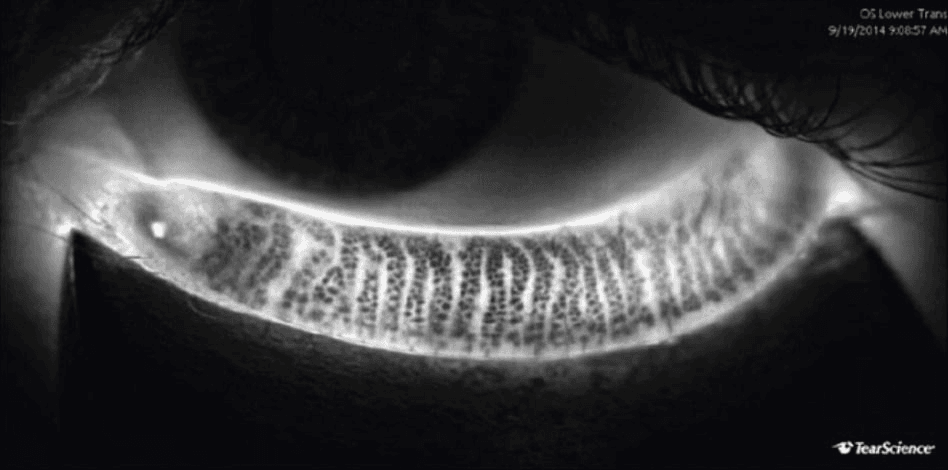

- Evaluacija Meibomovih žlezda – pregled otkriva eventualne promene u funkciji žlezda koje luče lipidni sloj suznog filma.